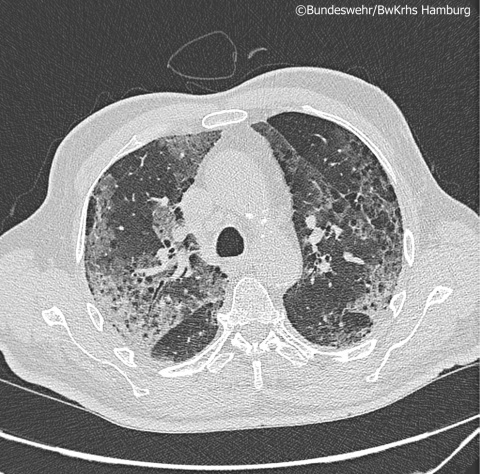

Im Rahmen der SARS-CoV-2 Pandemie wurden im Bundeswehrkrankenhaus (BwKrhs) Hamburg zahlreiche Patienten mit diesem neuartigen Krankheitsbild behandelt. Es bot sich ein sehr heterogenes Patientenkollektiv mit verschiedensten klinischen Verläufen, teilweise schweren Komplikationen und einigen Todesfällen. In einem stetigen Lernprozess wurden hausinterne fachübergreifende Therapie- und Überwachungsstandards erarbeitet. Unter anderem wurde auf der Basis von internationalen Publikationen sowie eigener Erfahrungen eine laborchemische Verlaufsroutine etabliert, um frühzeitig die häufigsten Komplikationen erkennen und behandeln zu können. Hierzu zählen vorrangig bakterielle Superinfektionen, thromboembolische Ereignisse und kardiale Komplikationen. Die folgende Kasuistik soll exemplarisch einen schweren Verlauf von COVID-19 mit kardialen Komplikationen beleuchten.